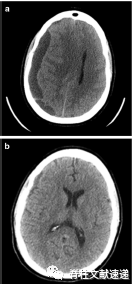

图注:55岁女性,腰椎翻修手术硬膜撕裂,术后第7天出现神经系统变化(神志错乱、失语等)。头颅CT示左侧额叶、顶叶、颞叶有硬膜下血肿,中线移位。患者被紧急送至手术室进行硬膜下血肿的清除。手术后失语症完全消失,头颅CT显示左侧血肿完全清除。